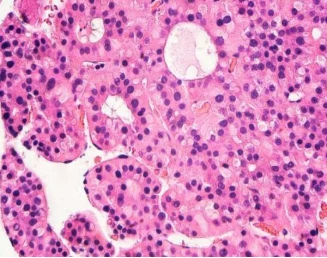

In this study, the researchers found that the way in which talin protein expands with exercise may be the determinant of DLC1 activity, so it is very important in the process of hepatocellular carcinoma. Under appropriate conditions, such as specific gene activation or decreased function of the body's immune system, cancer cells will migrate or metastasize to other tissues, which will promote the spread of cancer, once the cancer spreads to the secondary sites of the body, Researchers are hard to deal with, so effective cancer prevention is the first thing researchers should do.

Just like the skeleton controlled by external forces, cells can also react to external forces and contract and move. For example, the inner structure of the cytoskeleton can generate some force to help cancer cells migrate. The talin protein can adsorb to the cell membrane and build a "bridge" inside and outside the cell, which is coiled like a spring to be able to sense and react to mechanical forces in time. These forces change the shape of the talin protein, which inactivates DLC1, so that its DLC1 can not control the tumor suppressor function, which can promote cancer progression. The researchers are not aware of how the talin protein completes the shape change process.

The researchers studied the pattern of talin protein response to exercise in fibroblasts. Fibroblasts can help heal wounds and repair damaged tissues. If no inhibition is applied, fibroblasts produce scar tissue in the liver. , thereby inducing cirrhosis and hepatocellular carcinoma.